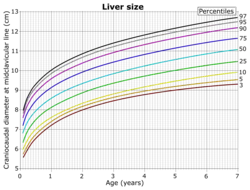

Abdominal ultrasonography of the liver, as a sagittal plane through the midclavicular line, with some standard measurements[2]

Right lobe of the liver at the midclavicular line at ages 0 to 7[16]

On abdominal ultrasonography, the liver can be measured by the maximum dimension on a sagittal plane view through the midclavicular line, which is normally up to 18 cm in adults.[2] It is also possible to measure the cranio-caudal dimension, which is normally up to 15 cm in adults.[2] This can be measured together with the ventro-dorsal dimension (or depth), which is normally up to 13 cm.[2] Also, the caudate lobe is enlarged in many diseases. In the axial plane, the caudate lobe should normally have a cross-section of less than 0.55 of the rest of the liver.[2]

Other ultrasound studies have suggested hepatomegaly as being defined as a longitudinal axis > 15.5 cm at the hepatic midline, or > 16.0 cm at the midclavicular line.[17][18]